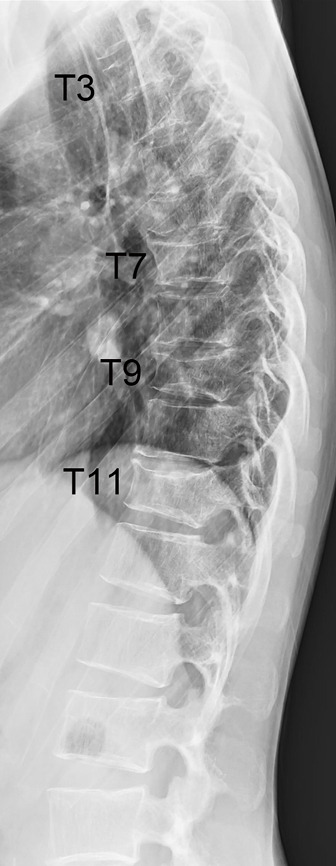

背景:妊娠和哺乳期相关骨质疏松症(PLO)是一种罕见的影响妊娠晚期和哺乳期早期妇女骨骼脆弱的疾病。PLO患者经历多发、快速发作的椎体骨折并发展为后凸,当诊断和治疗延迟时,预后较差。由于没有针对PLO患者的标准治疗方案,治疗应单独计划。近年来,romosozumab已被公认为治疗严重骨质疏松症患者最有效的药物之一。因为它可以在短时间内显著增加绝经后骨质疏松症妇女的骨密度(BMD),它对治疗骨质疏松症进展迅速且骨折风险高的患者是有用的。在这里,我们报告一例PLO合并多椎体骨折用romosozumab治疗。据我们所知,这是首个单独使用romosozumab治疗PLO的报道。病例描述:一名中年产后和哺乳期妇女在怀孕9个月时背部疼痛,分娩后恶化。PLO的诊断基于多发胸椎和骶骨脆性骨折和低骨密度。她接受罗莫索单抗治疗,背部疼痛逐渐消退。经过12个月的罗莫索单抗治疗,她的腰椎骨密度比基线增加了22.1%,并且没有发生进一步的骨折。结论:12个月的romosozumab治疗成功改善了重症PLO患者的临床状况,BMD显著增加。

Case description: A middle-aged postpartum and lactating woman experienced back pain at 9 months of pregnancy, which worsened after delivery. PLO was diagnosed based on multiple thoracic vertebral and sacral fragility fractures and low BMD. She was treated with romosozumab, and her back pain gradually subsided. After 12 months of romosozumab treatment, her lumbar spine BMD increased by 22.1% from baseline, and no further fractures occurred.